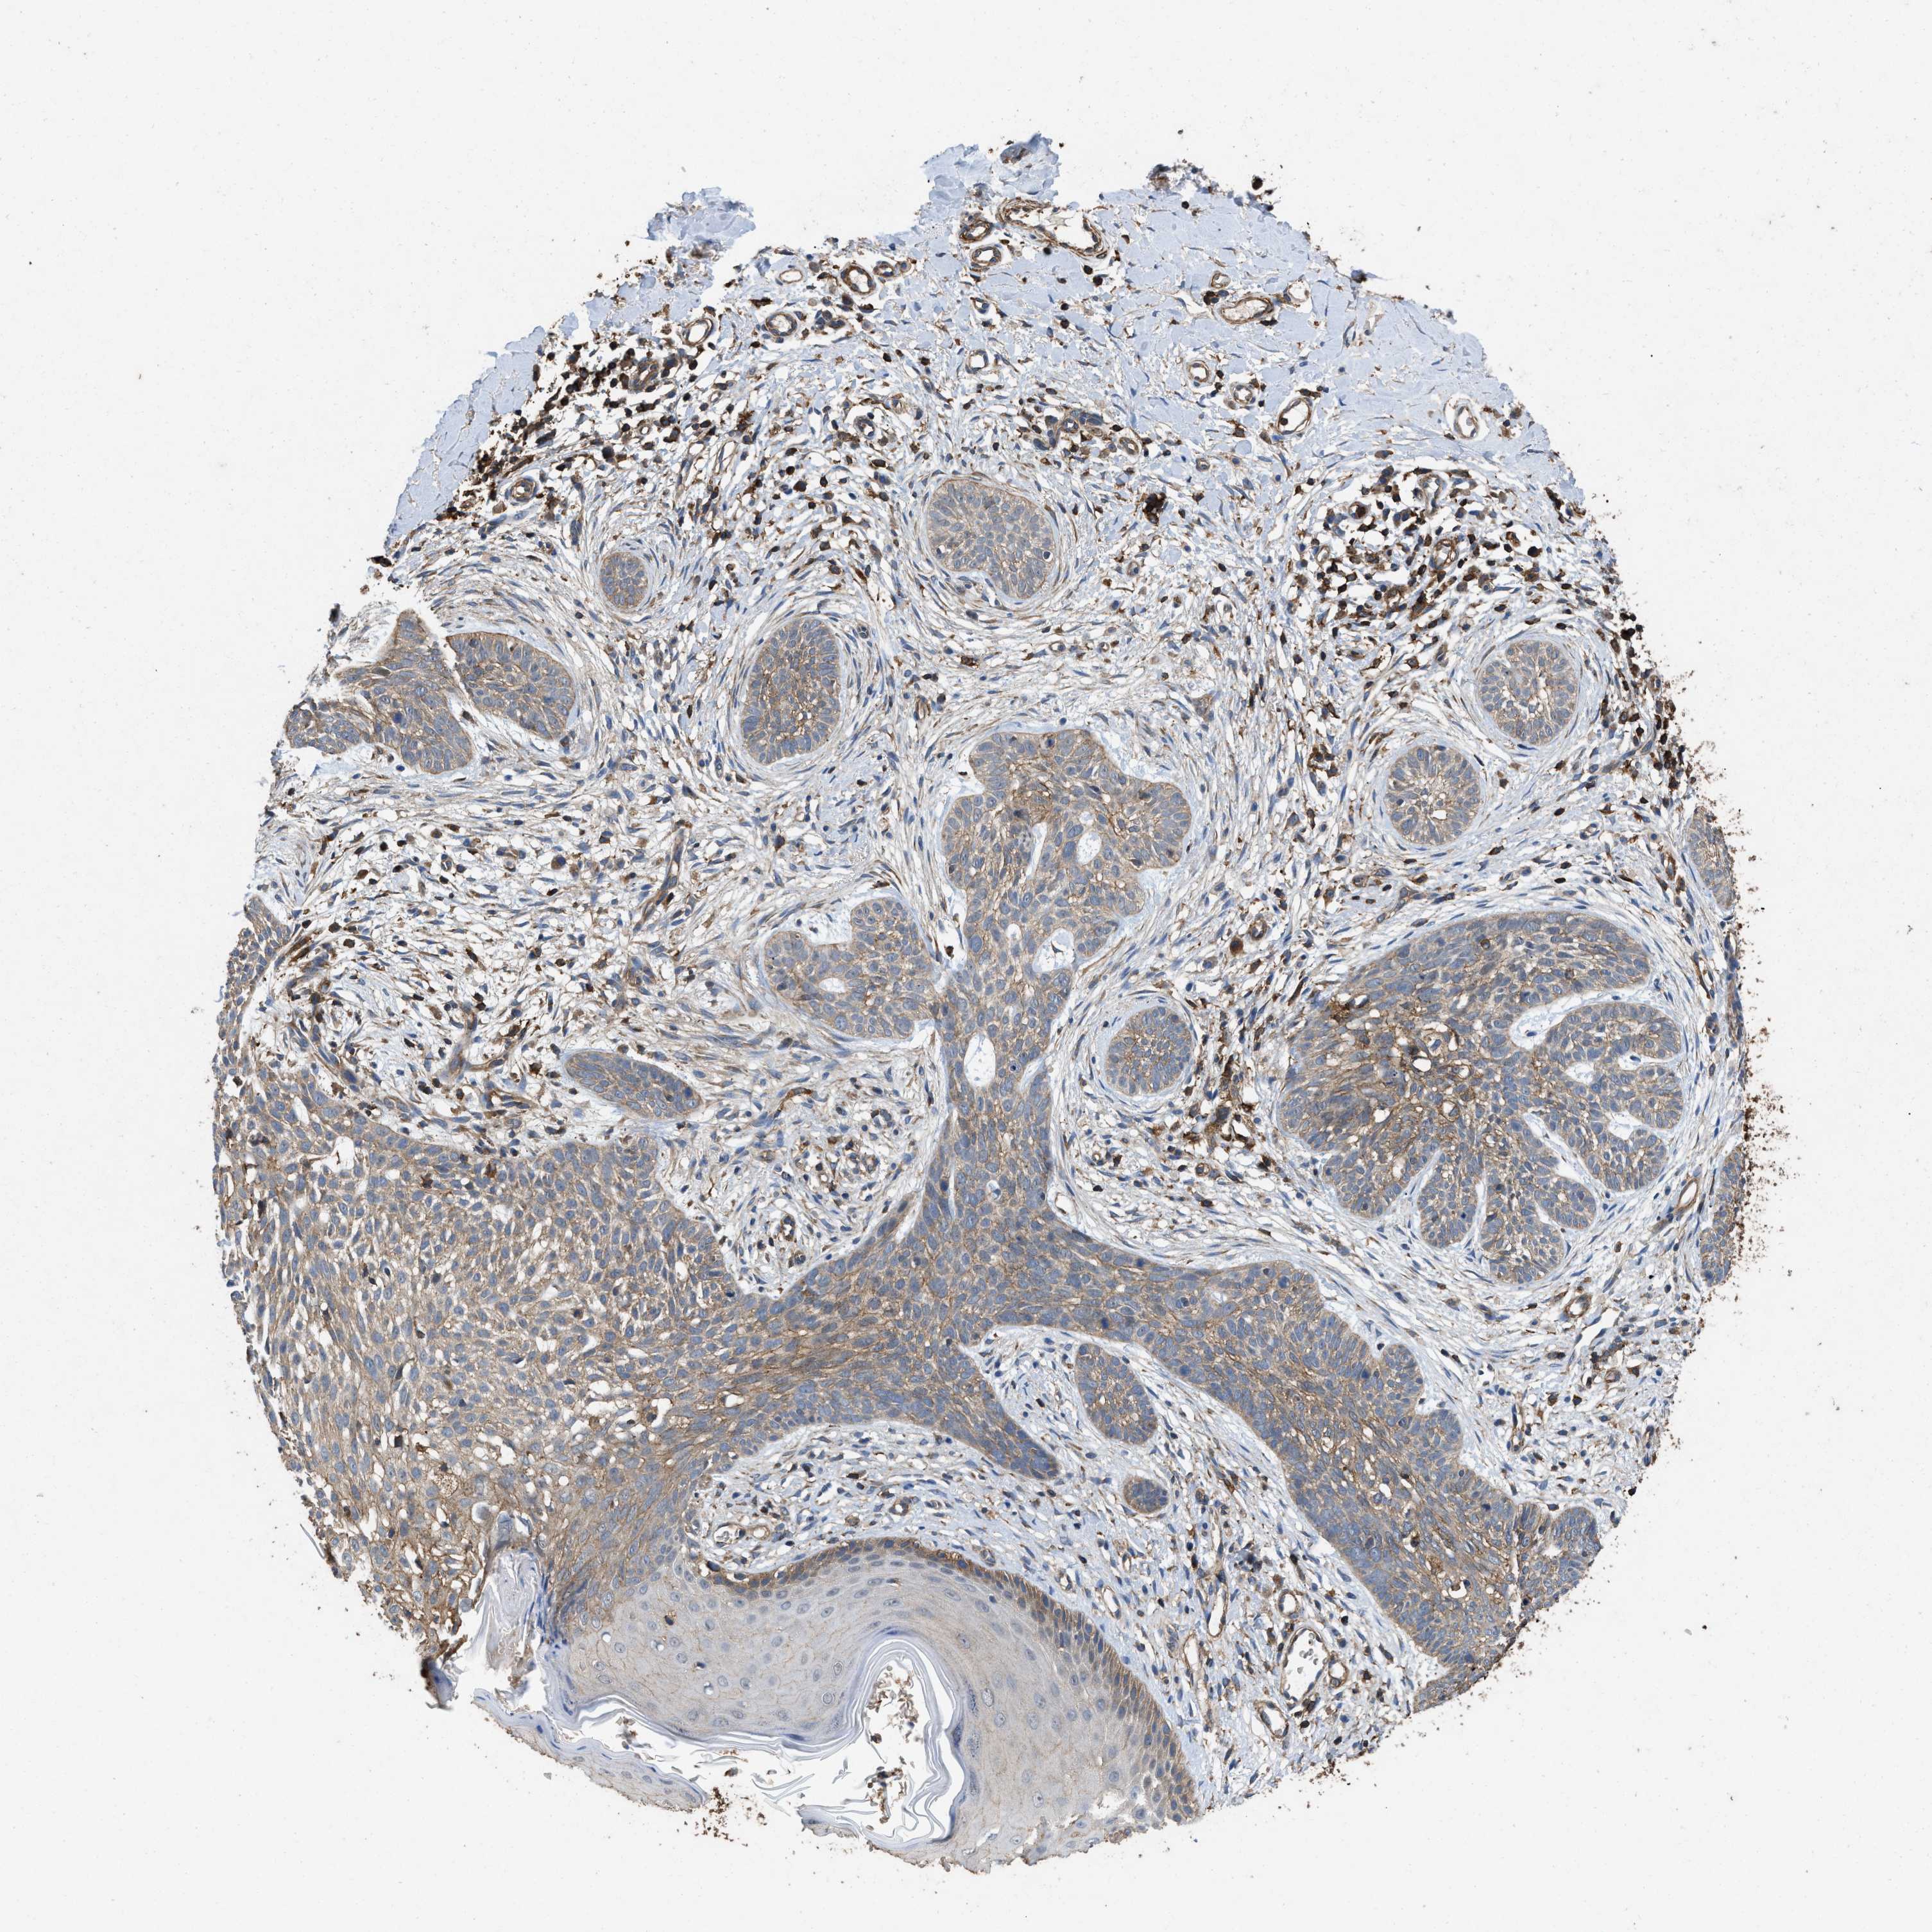

SKIN CANCER - Protein expressioni

A mouse-over function shows sample information and annotation data. Click on an image to view it in a full screen mode. Samples can be filtered based on level of antibody staining by selecting one or several of the following categories: high, medium, low and not detected. The assay and annotation is described here.

Antibody stainingi

Antibody staining in the annotated cell types in the current human tissue is reported as not detected, low, medium, or high, based on conventional immunohistochemistry profiling in selected tissues. This score is based on the combination of the staining intensity and fraction of stained cells.

Each image is clickable and will lead to virtual microscopy that enables deeper exploration of all samples and also displays staining intensity scores, fraction scores and subcellular localization as well as patient and tissue information for each sample.

Antibody CAB025361

Squamous cell carcinoma, NOS